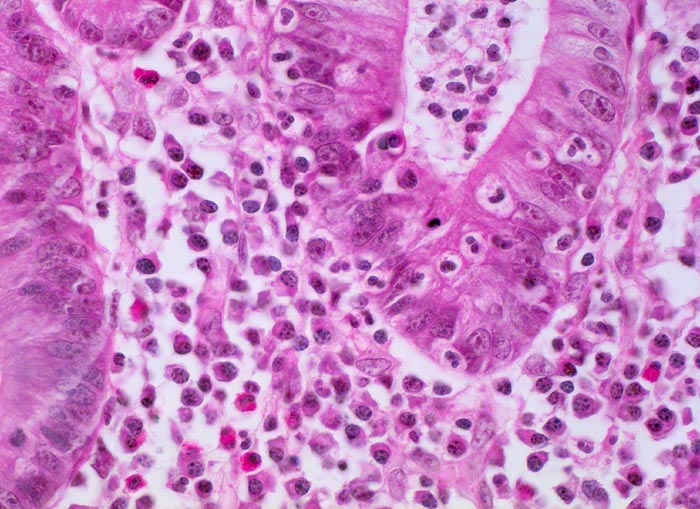

Die Colitis ulcerosa beginnt im Rektum (> 2758) und breitet sich kontinuierlich nach proximal aus. In 10% ist das gesamte Kolon (> 3364) befallen und es besteht zusätzlich eine back-wash-Ileitis im terminalen Ileum. Das Rektum ist bei unbehandelten Patienten praktisch immer befallen. Nach topischer Therapie kann das Rektum ausgespart sein und nach längerem Krankheistverlauf ist auch ein segmentaler Befall möglich. Bei fehlenden klinischen Angaben (Dauer der Erkrankung, Therapie) können diese atypischen Manifestationen diagnostische Schwierigkeiten verursachen. Makroskopisch finden sich häufig longitudinal ausgerichtete Ulzera mit Querverbindungen und Konfluenz. Residuelle Schleimhautinseln imponieren als Pseudopolypen. In der Remissionsphase ist die Schleimhaut glatt und blass, das Faltenrelief ist vergröbert und verstrichen und es finden sich häufig Granulationsgewebspolypen. Mikroskopisch findet sich je nach Entzündungsaktivität eine mehr oder weniger ausgeprägte diffuse Verdichtung des lymphoplasmazellulären Entzündungsinfiltrates mit Beimischung von Granulozyten in Form einer Kryptitis oder von Kryptenabszessen. Bei einer stark aktiven Entzündung finden sich zusätzlich Erosionen und Ulzera mit Ausdehnung der Entzündung über die Mukosa hinaus in die Submukosa oder in noch tiefere Schichten bei hochflorider Kolitis. Die Kryptenarchitektur ist gestört, die Anzahl der Krypten und der Becherzellen vermindert. In der Regeneratphase finden sich zahlenmässig reduzierte und verkürzte Krpyten mit normaler Anzahl Becherzellen. Meist bleibt eine leichte Verdichtung der Entzündungszellen in der Lamina propria bestehen.

Morphologische Merkmale:

• Abwechslungsweise oberflächliche Ulzera und pseudopolypöse Schleimhautvorwölbungen.

• Entzündungsinfiltrate in Mukosa und Submukosa.

• Unregelmässig geformte und verzweigte Krypten (Kryptenarchitekturstörung).

• Krpyten enden deutlich oberhalb der Lamina muscularis mucosae (Kryptenatrophie).

• Verminderte Schleimbildung und Becherzellverlust.

• Basal betonte Plasmozytose und Infiltrate neutrophiler Granulozyten.

• Ansammlungen neutrophiler Granulozyten in Kryptenlumina (=Kryptenabszesse) und Infiltrate von neutrophilen Granulozyten im Kryptenepithel (=Kryptitis).